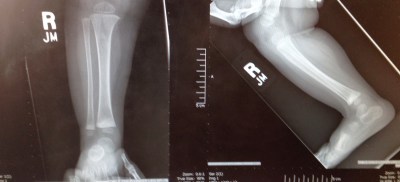

![]() |

| That time we broke Clara’s leg and the cutest x-rays of all time were taken. |